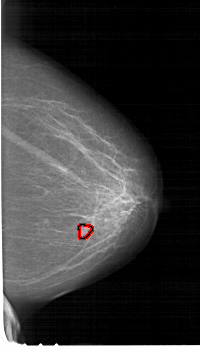

FILE: A_1729_1.RIGHT_MLO.OVERLAY

TOTAL_ABNORMALITIES 1

ABNORMALITY 1

LESION_TYPE CALCIFICATION TYPE PLEOMORPHIC DISTRIBUTION CLUSTERED

ASSESSMENT 4

SUBTLETY 3

PATHOLOGY MALIGNANT

TOTAL_OUTLINES 1

BOUNDARY